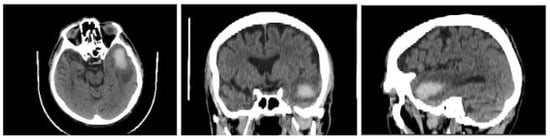

| ICH Volume [cm] after First Diagnosis | ICH Volume [cm] after a Week | Approximate Percentage Change of ICH Volume after Week [%] | |

|---|---|---|---|

| Patient 1 | 17.0607 | 7.7141 | −55 |

| Patient 2 | 76.4668 | 33.1258 | −57 |

| Patient 3 | 17.5321 | 8.2503 | −53 |

| Patient 4 | 8.5965 | 0 | −100 |

| Patient 5 | 52.9358 | 26.0897 | −51 |